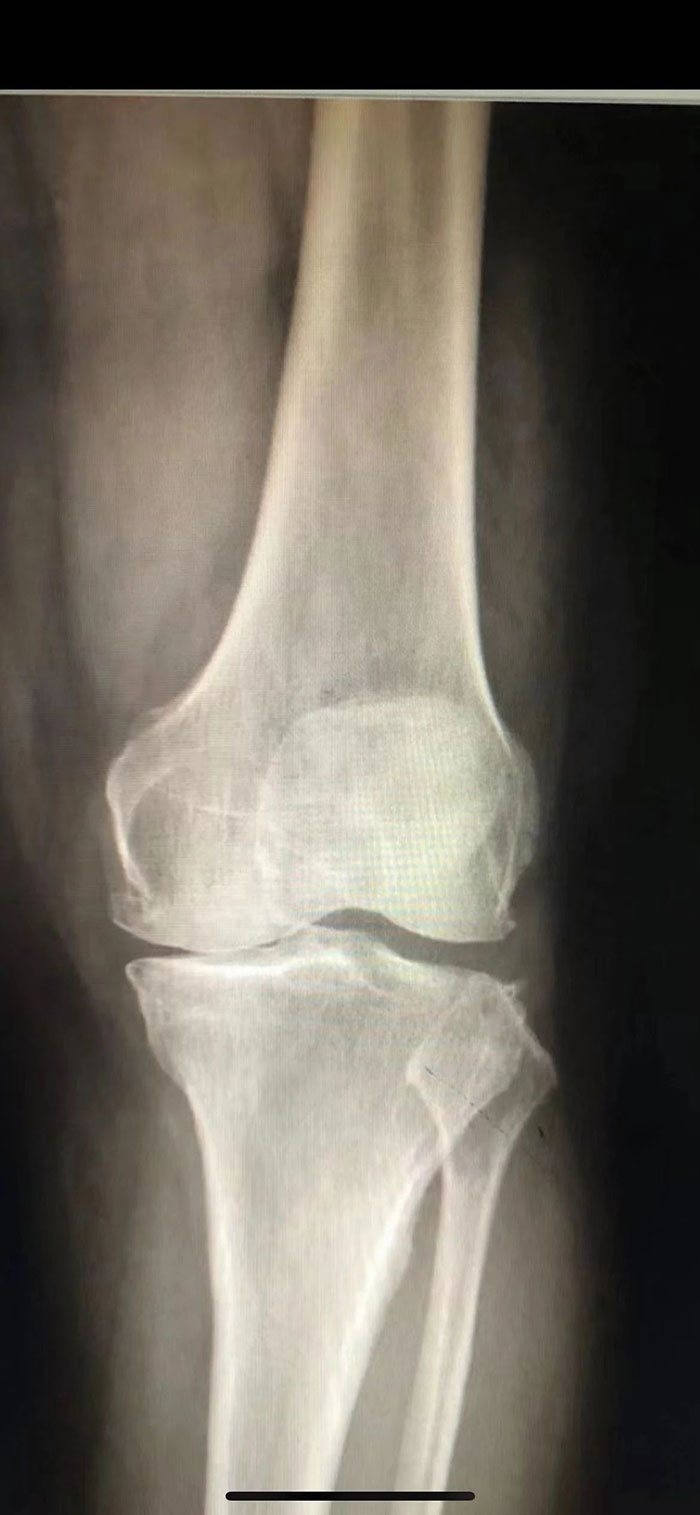

近日,滄州市中心醫(yī)院關節(jié)外三科(骨六科)成功為一名左膝關節(jié)前內側關節(jié)炎高齡患者完成左膝關節(jié)單髁保膝術。

來自獻縣75歲的王大娘因過度勞累,近年來出現左膝關節(jié)疼痛的情況,一開始休息還能暫時緩解,慢慢地開始用止痛藥都沒有了效果,特別是上下樓梯、上下坡明顯加重。難以忍受的疼痛已經嚴重影響到了她的日常生活,王大娘曾在多家醫(yī)院就診治療,效果都不盡如人意。家人得知滄州市中心醫(yī)院關節(jié)外三科(骨六科)治療骨關節(jié)疾病的效果非常好,于是抱著一線希望找到了關節(jié)外三科(骨六科)主任張磊。

張磊主任經過仔細地了解病史、檢查發(fā)現,王大娘左側膝關節(jié)退變,關節(jié)面磨損嚴重,且股骨內側髁有骨壞死,疼痛明顯。“以患者目前的情況來看,左膝關節(jié)內側關節(jié)面磨損嚴重,癥狀也是以內側為主,診斷為左膝關節(jié)前內側關節(jié)炎,可行左膝關節(jié)單髁保膝手術,改善疼痛,恢復行走能力?!痹谂c患者及其家屬詳細溝通后,經討論,張磊決定為其實施左膝關節(jié)單髁保膝手術,盡全力為王大娘保留膝關節(jié)的同時解除病痛的折磨。聽到這個消息后,王大娘的眼里又重新燃起了希望。